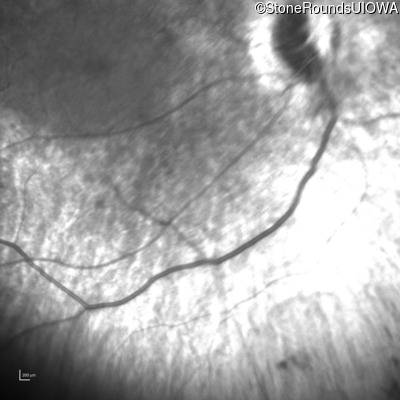

Infrared Fundus Photograph - Right - No Light Perception

Exemplar